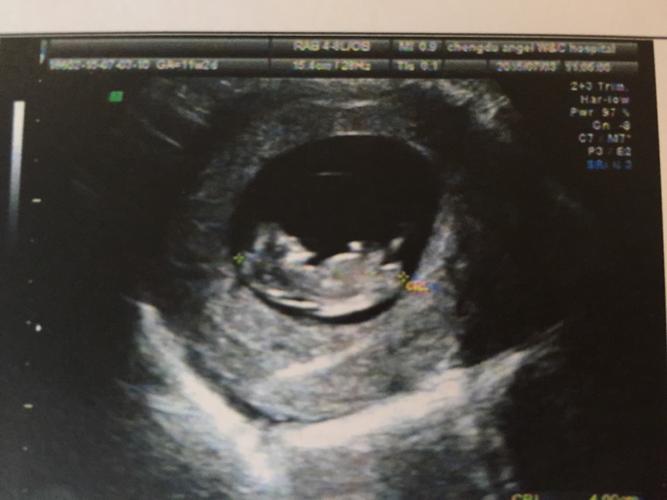

![11周胎儿图男孩子,怀孕11周男孩b超图 13楼 2015-7-3 孕11周 2小宝宝好可爱[爱心]心率170/分好快的呢](https://ss3.baidu.com/-fo3dSag_xI4khGko9WTAnF6hhy/zhidao/pic/item/d01373f082025aaf24f82158fdedab64024f1a5e.jpg)

13楼 2015-7-3 孕11周 2小宝宝好可爱[爱心]心率170/分好快的呢